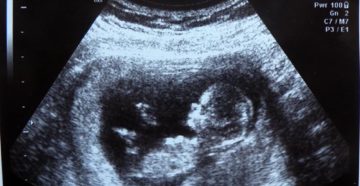

11 неделя беременности Развивающаяся беременность на 11 неделе приносит ощутимые перемены в тело женщины и…

11 неделя беременности: что происходит с малышом и мамой, признаки осложнений, необходимые анализы + отзывы…

11 неделя беременности: что происходит в организме женщины и с плодом, исследования и осложнения на…

11 неделя беременности: развитие крохи и токсикоз гудбай Здравствуйте, дорогие читательницы! Совсем скоро завершится 1…